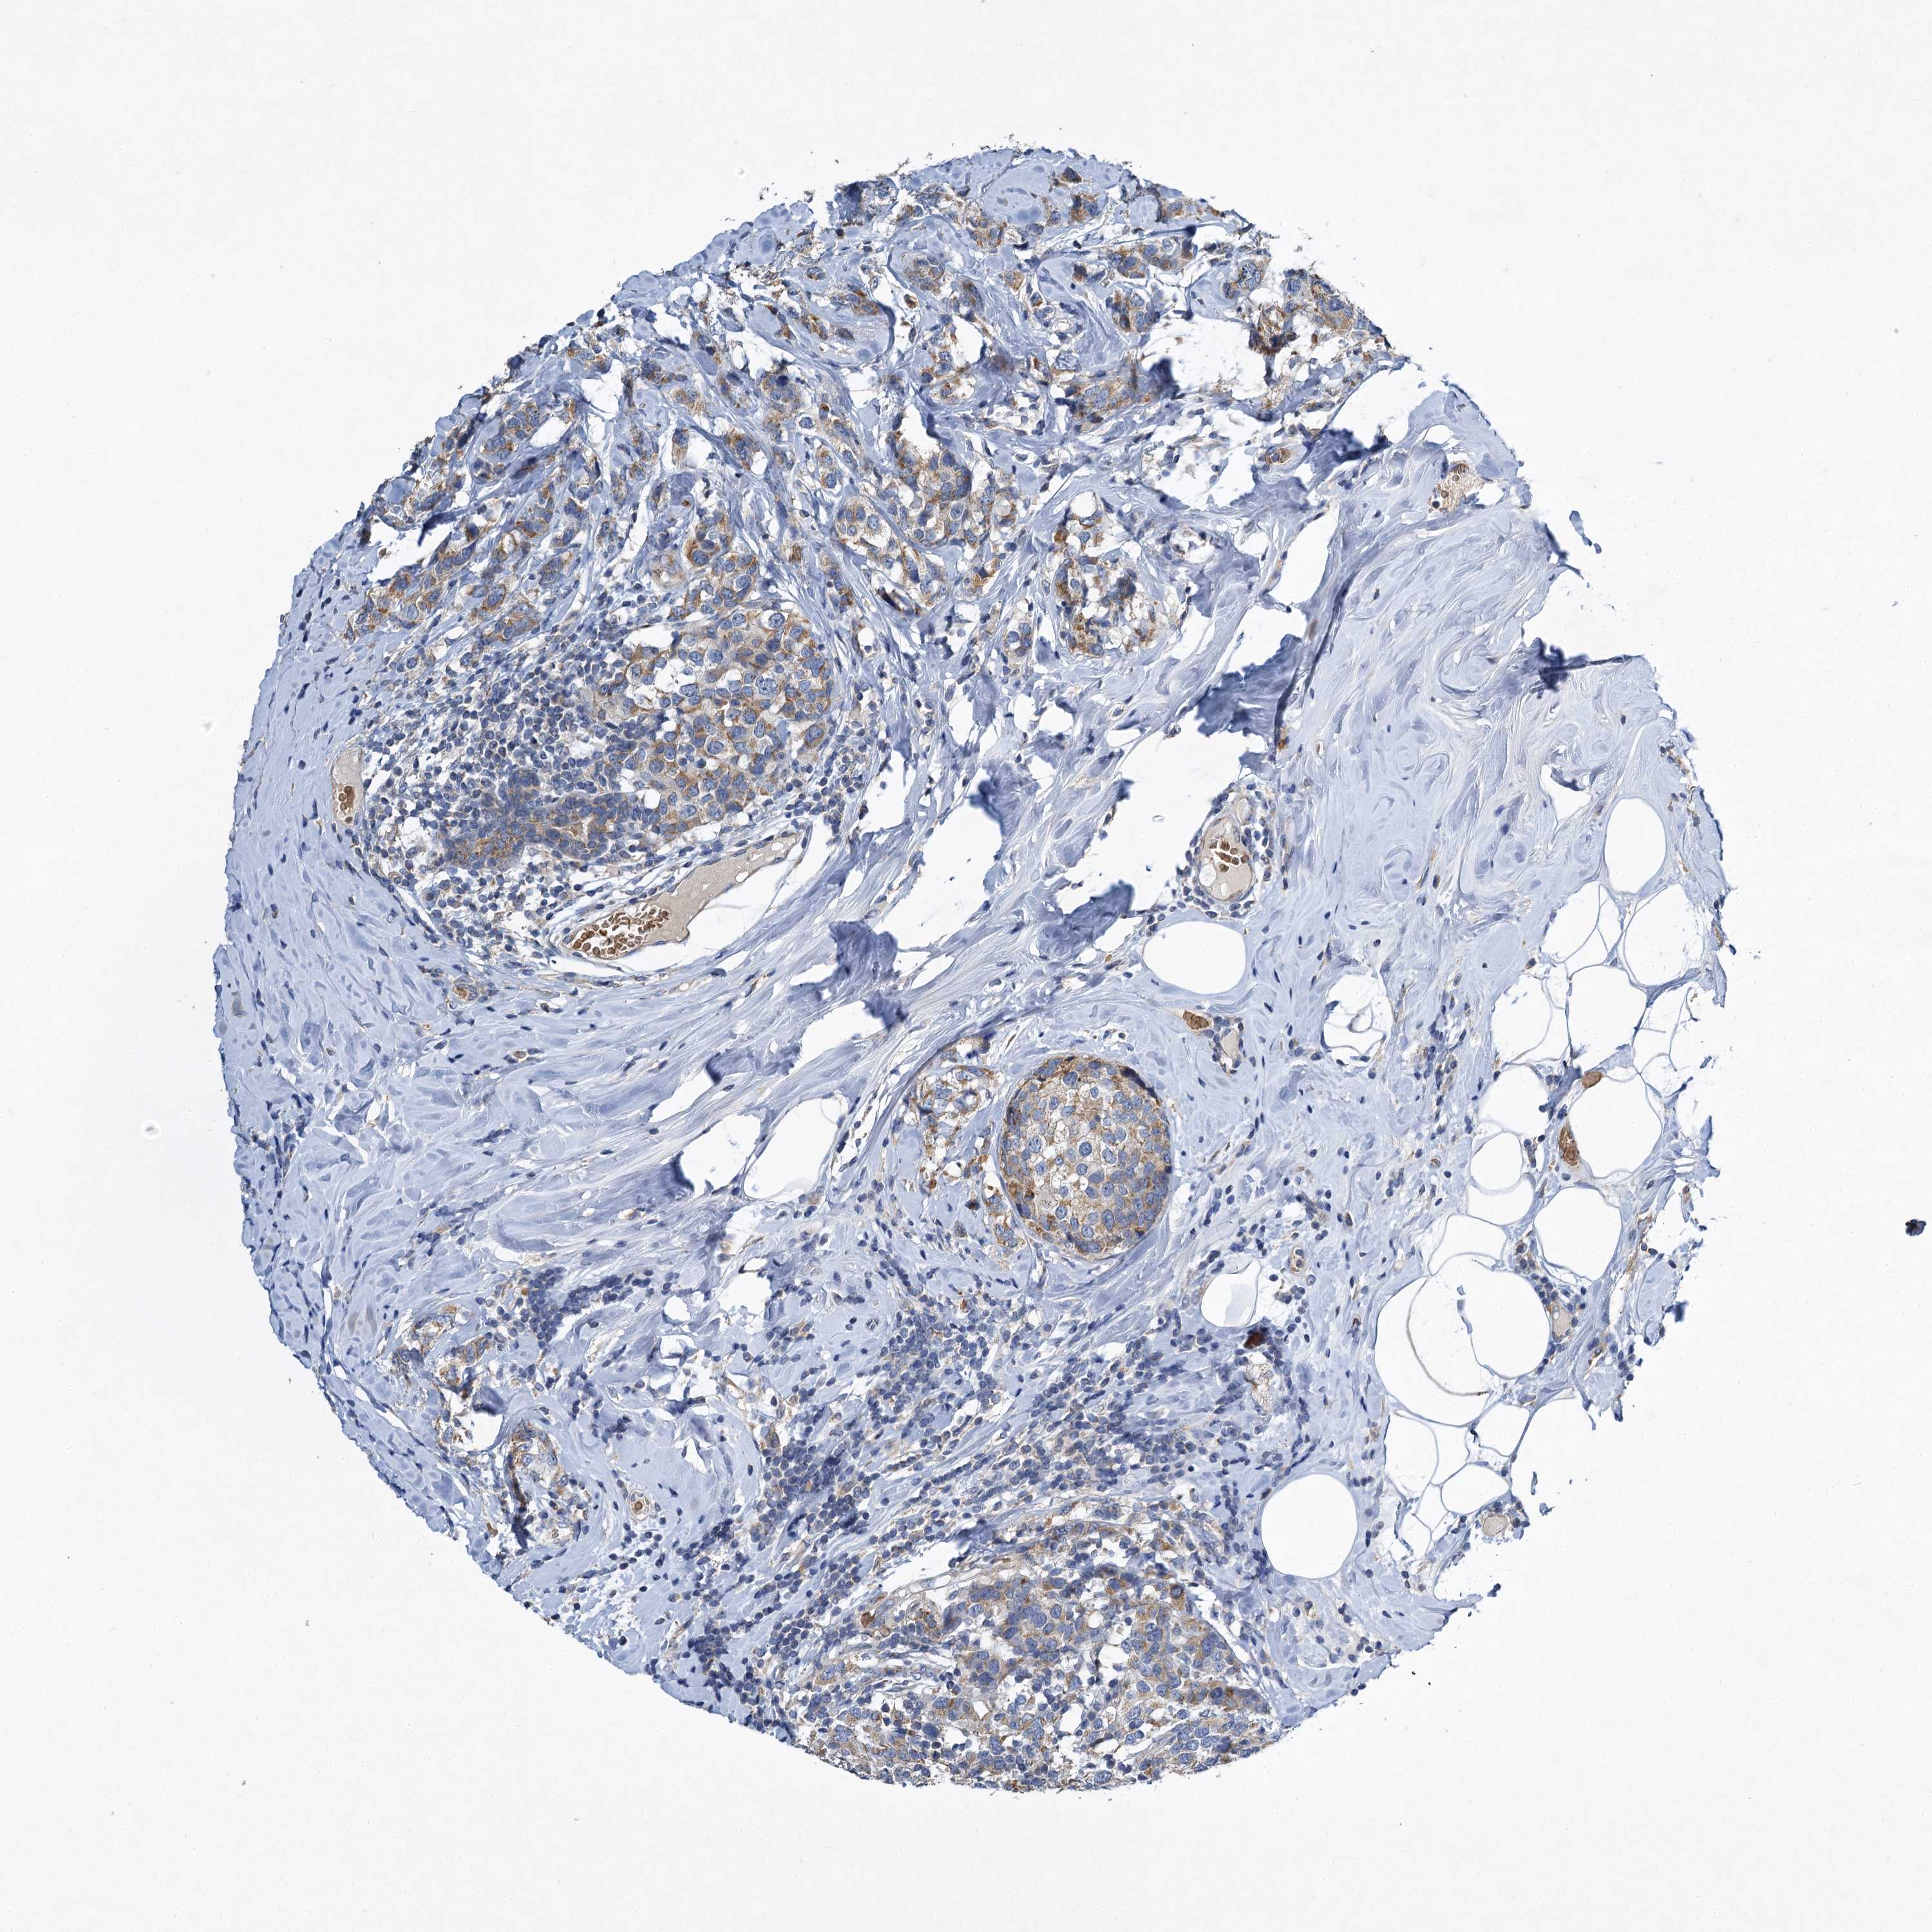

BRCA TCGA BRCA VALIDATION PROTEIN EXPRESSION